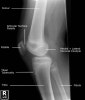

소아 무릎, 아래 다리의 X-ray2017-02-25카테고리 103원본 보기 Knee Paediatric Protocol : AP, Lateral Knee lateral view Knee AP view Tibia/Fibula AP/Lateral view ← 이전 글내족지 보행(In-toeing gait) : 아이가 안짱다리 모양의 걸음걸이를 보여요다음 글 →소아 발목의 X-ray같은 카테고리 글2017-02-26소아 발목의 X-ray2017-02-18소아의 골반, 고관절, 대퇴골의 X-ray2017-02-14손목 성장판 골단판 골절(Epiphysiolysis fracture)← 전체 글로 돌아가기